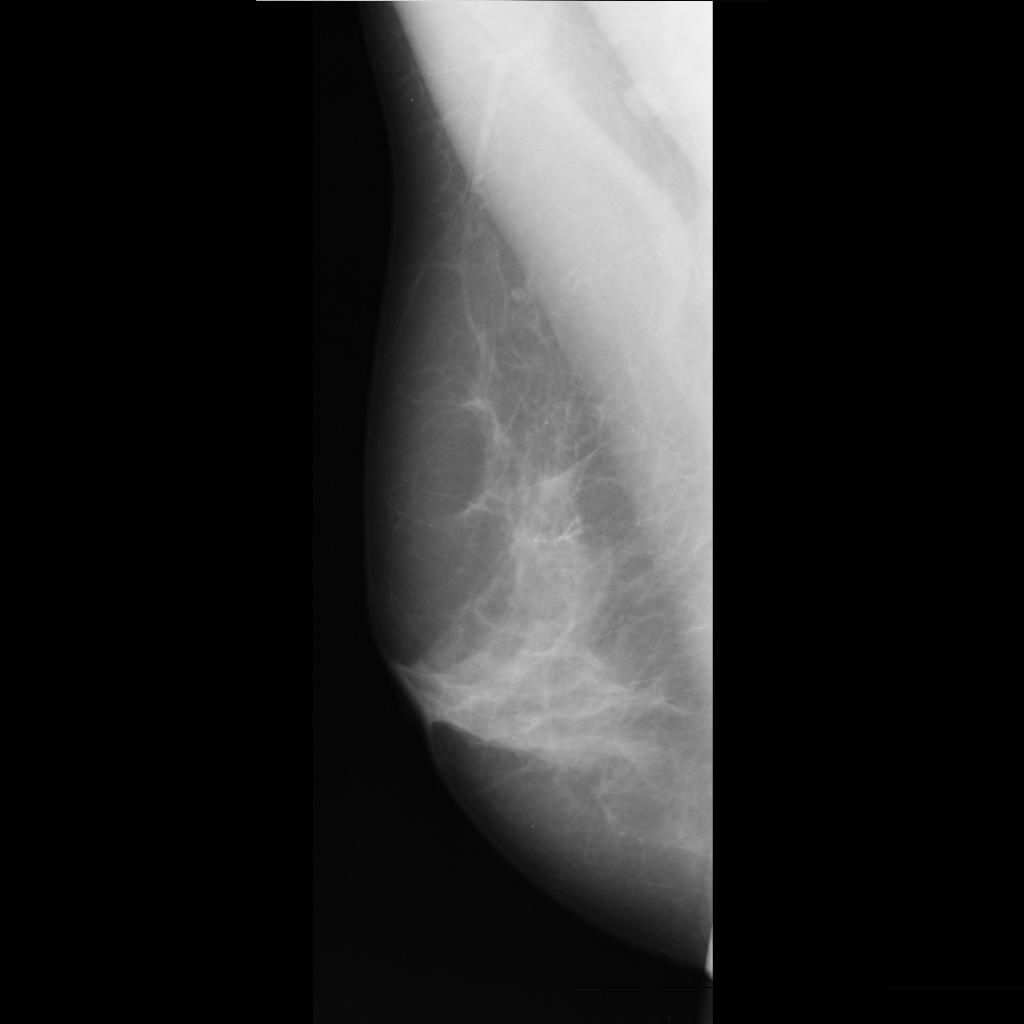

benign